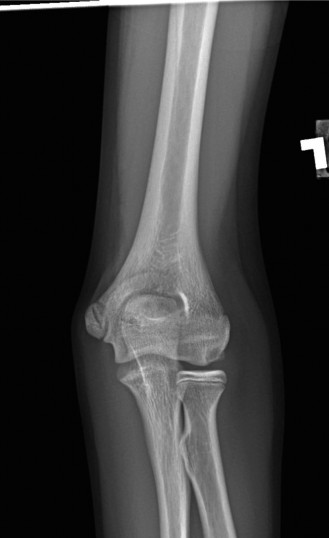

A sophomore, high school wide receiver presents to your clinic at the beginning of his football season. He reports a dislocation event after being tackled; his shoulder was “put back in place” by the on-field athletic trainer. A CT scan taken in the hospital today is shown (Fig. 2–33). He has been recruited by numerous colleges, plans to play at a division 1 school, and is very eager to return to the field.

Figure 2–33

The correct answer is (E). A large bony fragment (>20%) makes the failure rate with nonoperative treatment (Answers A, B) unacceptably high. This question is meant to illustrate the challenges associated with treating an in-season athlete and highlighting the indications for surgery after a first time dislocation event. Typically, early in a season, providers will initiate an aggressive PT program and try and return athletes to the field within a few weeks so that they can play out the remainder of the season. Towards the end of the season, when there is insufficient time to rehab a patient, one may choose early surgery so that the patient has maximal time to recover prior to the next season. In this case, even though the

patient is extremely motivated to return to the field and has only sustained a single dislocation event, the large bony Bankart lesion behooves surgical treatment. The best option for him would be to have early surgery and have a maximal amount of time to prepare for his senior season. A Latarjet procedure (Answer C) is used for patients with recurrent anterior instability and significant glenoid bone loss, and the Magnuson–Stack procedure (Answer D) is a largely historic procedure that was used for recurrent anterior instability. Objectives: Did you learn...? The common presentation of a patient with shoulder instability?